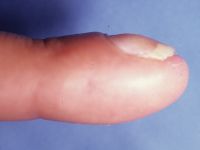

| Late films show only palmar cortical bridging and a lucency in the distal phalanx which was visible in the original films, consistent with an epidermal inclusion cyst. The patient admitted to many open and crushing fingertip injuries over the years in his line of work. |